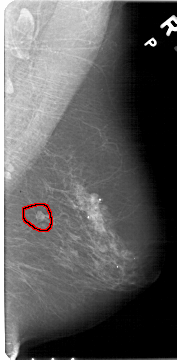

A_1457_1.RIGHT_CC

RIGHT_MLO LINES 5386 PIXELS_PER_LINE 2641 BITS_PER_PIXEL 12 RESOLUTION 43.5 OVERLAY

FILE: A_1457_1.RIGHT_CC.OVERLAY

TOTAL_ABNORMALITIES 1

ABNORMALITY 1

LESION_TYPE MASS SHAPE LOBULATED MARGINS CIRCUMSCRIBED

ASSESSMENT 4

SUBTLETY 4

PATHOLOGY BENIGN

TOTAL_OUTLINES 1

BOUNDARY